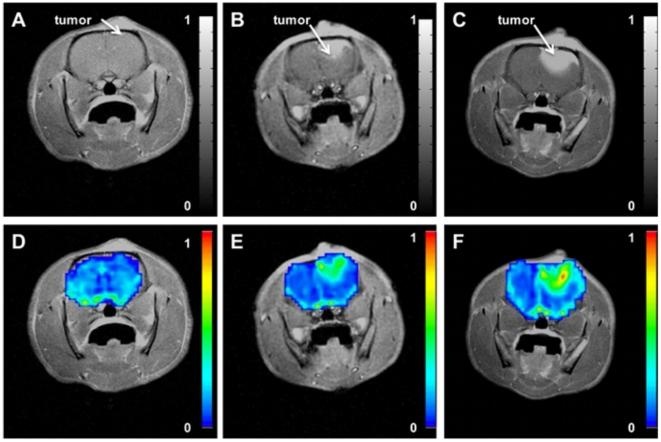

Multimodality imaging of abnormal vascular perfusion and morphology in preclinical 9L gliosarcoma model.

METHODOLOGY/PRINCIPAL FINDINGS: One cohort of Fisher 344 rats (N = 13), inoculated intracerebrally with 9L gliosarcoma cells, was treated with dexamethasone (i.p. 3 mg/kg/day) for five consecutive days, and another cohort (N = 11) was treated with equal volume of saline. Longitudinal DSC-MRI studies were performed at the first (baseline), third and fifth day of treatments. Relative cerebral blood volume (rCBV) was significantly reduced on the third day of dexamethasone treatment (0.65 ± .13) as compared to the fifth day during treatment (1.26 ±.19, p < 0.05). In saline treated rats, relative CBV gradually increased during treatment (0.89 ±.13, 1.00 ± .21, 1.13 ± .23) with no significant difference on the third day of treatment (p>0.05). In separate serial studies, microfocal X-ray CT of ex vivo brain specimens (N = 9) and immunohistochemistry for endothelial cell marker anti-CD31 (N = 8) were performed. Vascular morphology of ex vivo rat brains from micro-CT analysis showed hypervascular characteristics in tumors, and both vessel density (41.32 ± 2.34 branches/mm(3), p<0.001) and vessel tortuosity (p<0.05) were significantly reduced in tumors of rats treated with dexamethasone compared to saline (74.29 ± 3.51 branches/mm(3)). The vascular architecture of rat brain tissue was examined with anti-CD31 antibody, and dexamethasone treated tumor regions showed reduced vessel area (16.45 ± 1.36 µm(2)) as compared to saline treated tumor regions (30.83 ± 4.31 µm(2), p<0.001) and non-tumor regions (22.80 ± 1.11 µm(2), p<0.01).

CONCLUSIONS/SIGNIFICANCE: Increased vascular density and tortuosity are culprit to abnormal perfusion, which is transiently reduced during dexamethasone treatment.